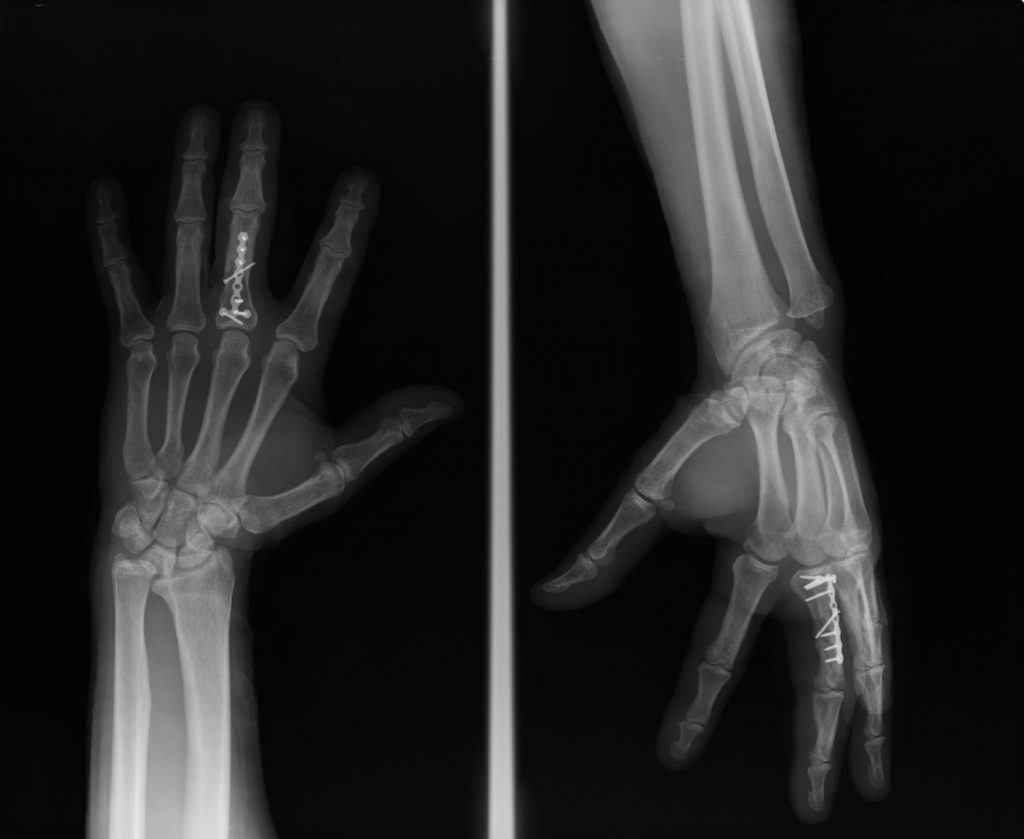

Figura 2 - Fractura falange 5º dedo desplazada. (Ver también Figura 6)

Otras fracturas pueden precisar cirugía para reconstruir la forma y posición del hueso (reducción abierta). Una vez que los fragmentos del hueso están en su sitio, se mantienen con clavos, placas o tornillos (Figuras 5, 6 y 7).

Figura 6 - Osteosíntesis con tornillos de Fractura falange 5º dedo desplazada.

Figura 7 - Osteosíntesis con placa y tornillos de falange proximal 3º dedo.